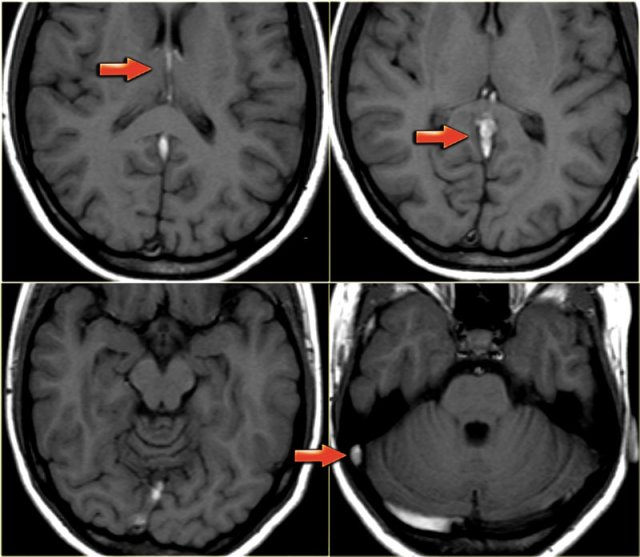

Venous infarction (4) - Deep cerebral veins

On the far left a FLAIR image demonstrating high signal in the left thalamus.

When you look closely and you may have to enlarge the image to appreciate this, there is also high signal in the basal ganglia on the right.

These bilateral findings should raise the suspicion of deep cerebral venous thrombosis.

On the left a young patient with bilateral abnormalities in the region of the basal ganglia.

Based on the imaging findings there is a broad differential including small vessel disease, demyelinisation, intoxication and metabolic disorders.

Continue with the T1-weighted images in this patient.

Notice the abnormal high signal in the internal cerebral veins and straight sinus on the T1-weighted images, where there should be a low signal due to flow void.

This was unlike the low signal in other sinuses.

The diagnosis is bilateral infarctions in the basal ganglia due to deep cerebral venous thrombosis.